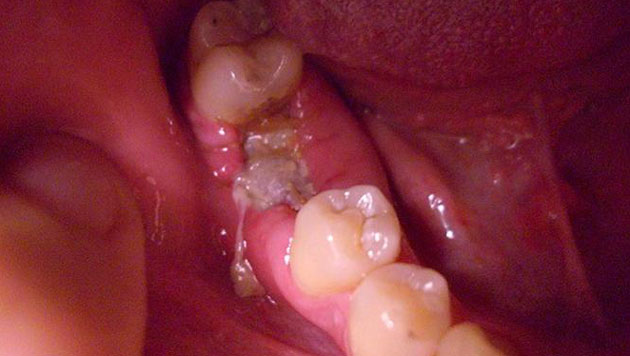

Отдавать болезненными ощущениями в скулу может даже тогда, когда имеет место обычный кариес или пульпит, периодонтит, стоматит или альвеолит, возникший вследствие удаления зуба. Ведь все органы челюстно-лицевого аппарата расположены в опасной близости друг от друга.

Хуже, когда простое стоматологическое заболевание долго оставалось невылеченным и инфекция начала распространяться дальше, дойдя до скуловой области лица. Тогда у вас уже могут болеть скулы от более серьезной патологии – остеомиелита. Заболевание поражает костную ткань челюсти, вызывая ее нагноение и некроз, сопровождается общим ухудшением самочувствия, поднимается температура тела, лицо может опухнуть и деформироваться.

«Остеомиелит верхней челюсти наблюдается во врачебной практике значительно реже, чем нижней. Тем не менее, заболевание считается очень опасным, т.к. его несвоевременное или неправильное лечение может привести к перелому челюсти, к сепсису, к поражению внутренних органов, к легочной недостаточности, флегмоне. Поэтому его необходимо лечить хирургически, дополнительно применять противовоспалительную терапию, антибиотики, лечить подвергшиеся патологическому процессу соседние органы и удалять пораженные зубы», – поясняет Цориева Э.О., терапевт, хирург.

Остеомиелит бывает разных видов: травматический, лучевой (возникает на фоне появления злокачественных раковых опухолей), гематогенный (инфекция попадает через кровь от соседних пораженных органов). Но чаще всего заболевание носит одонтогенный характер, т.е. является следствием запущенных кариеса, пульпита и других стоматологических проблем.